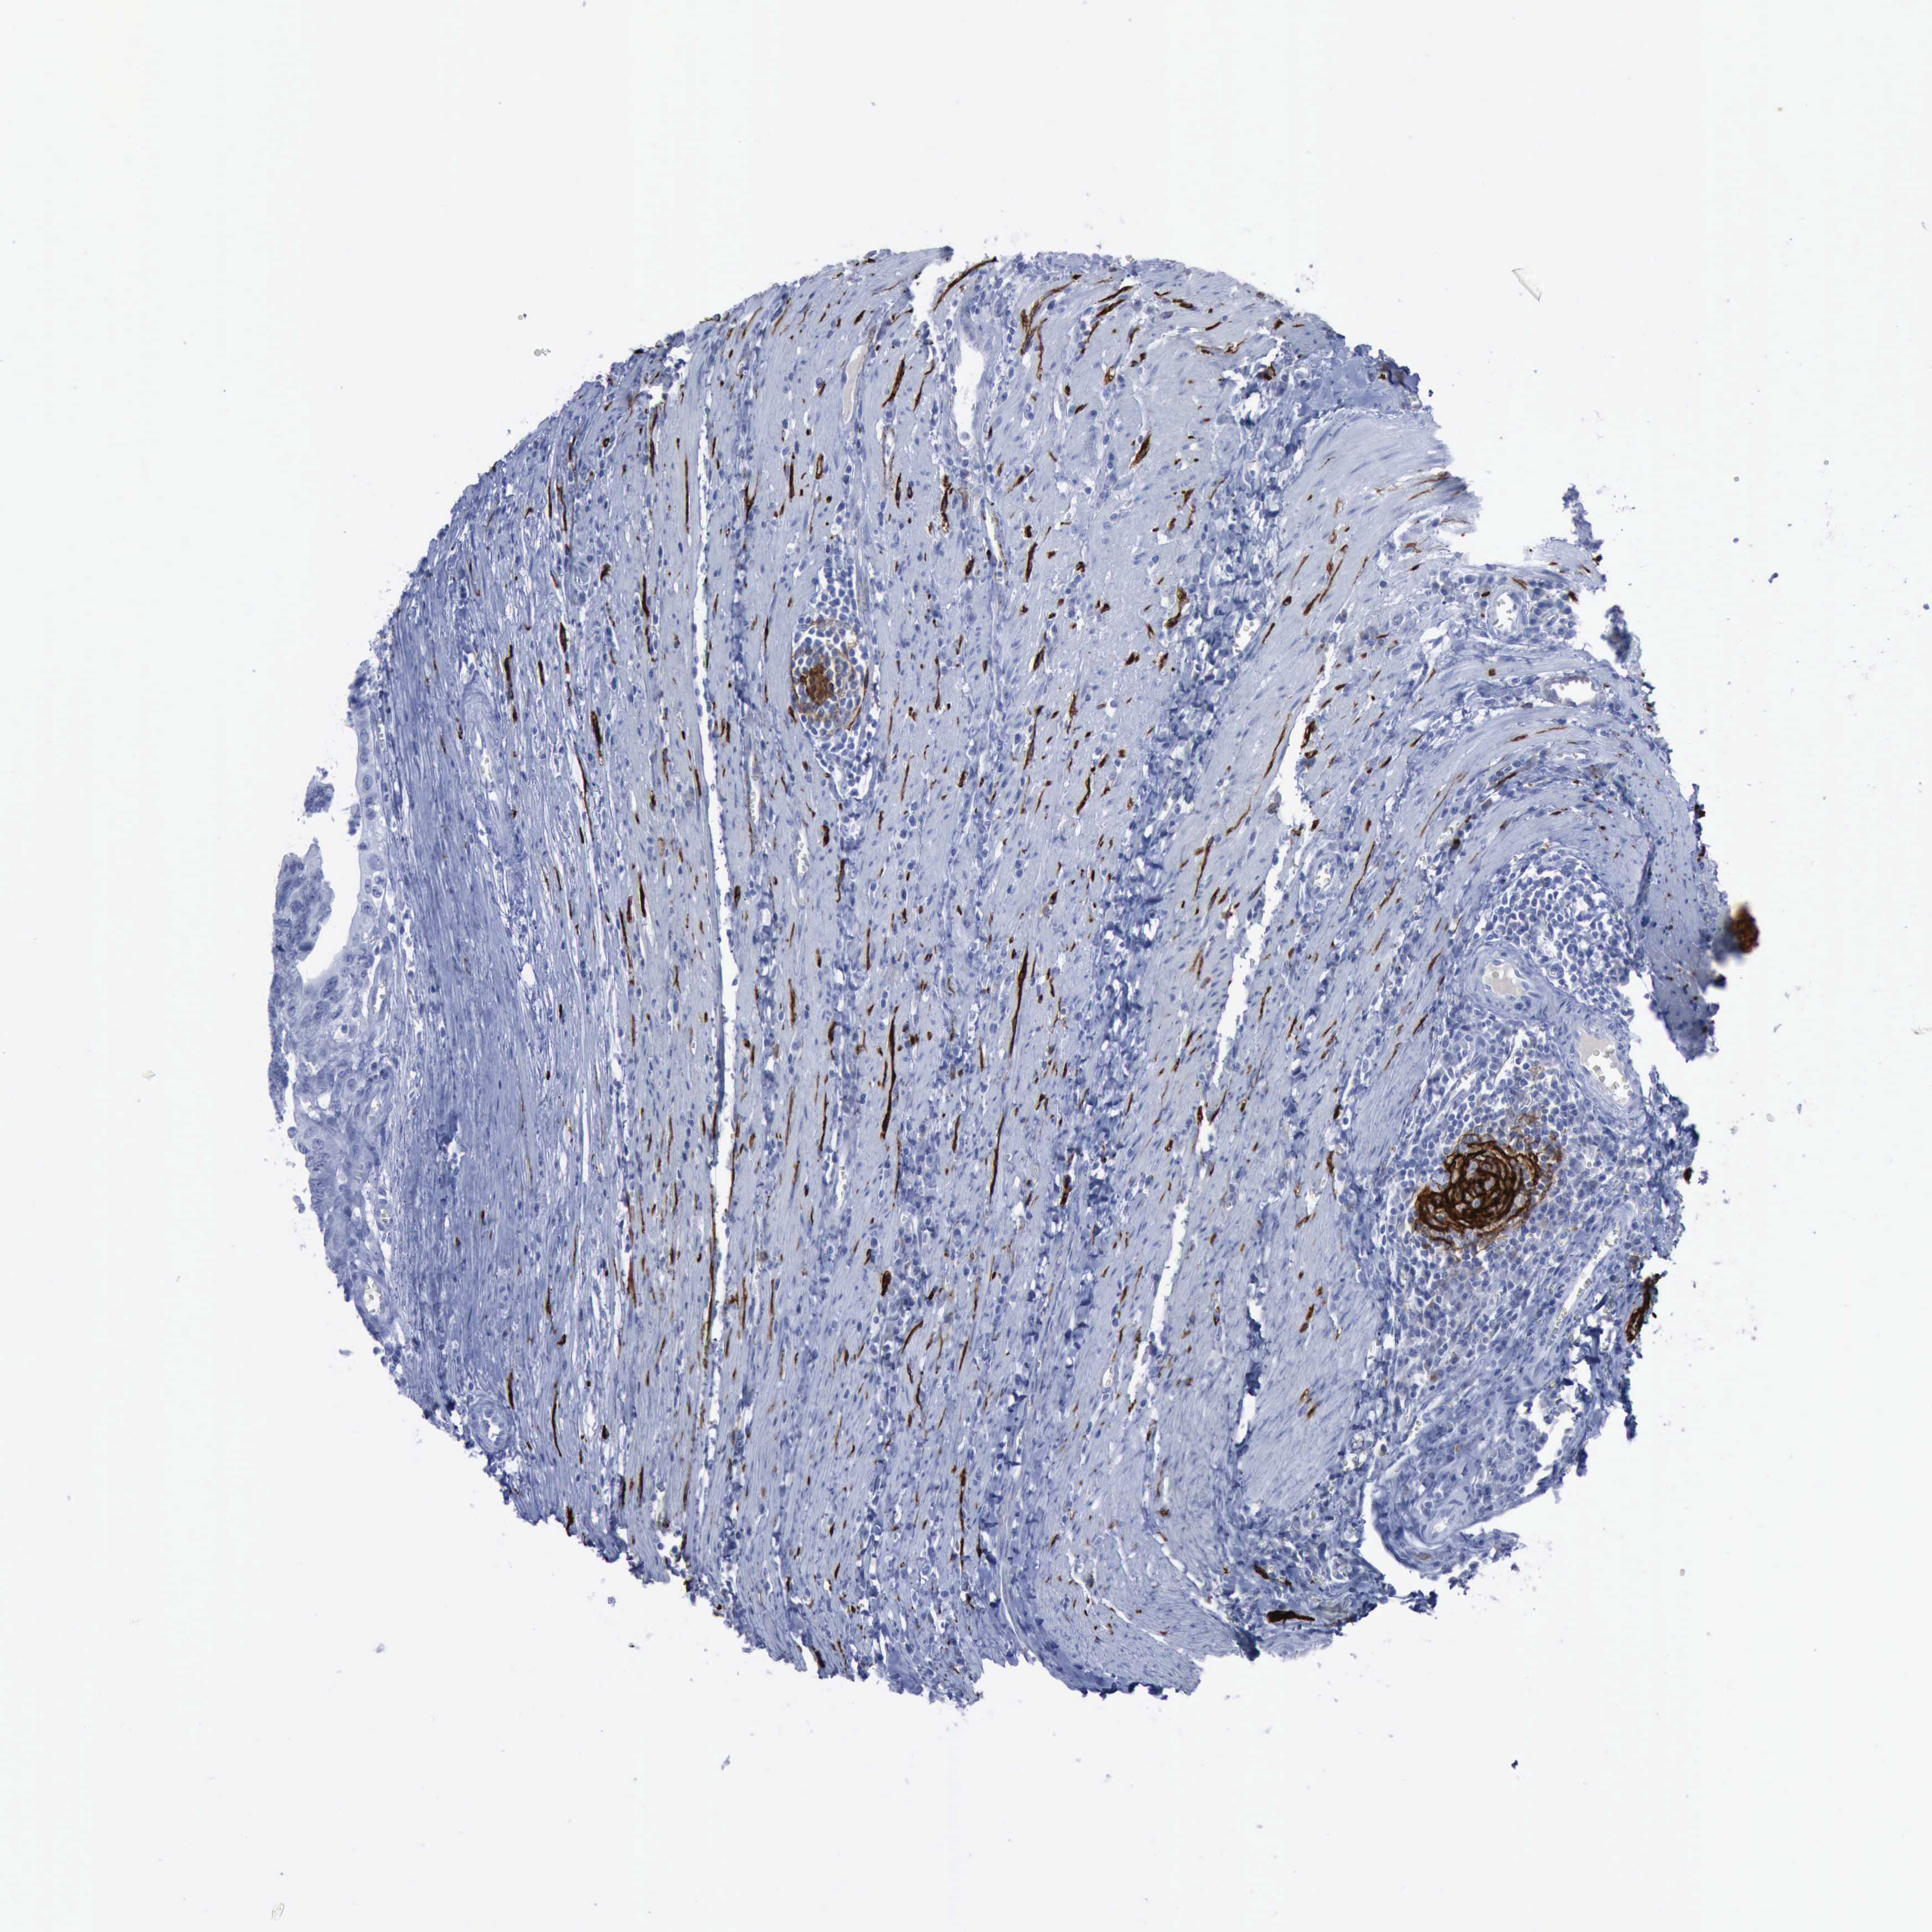

Colorectal cancer

Human cancer

Colon adenocarcinoma